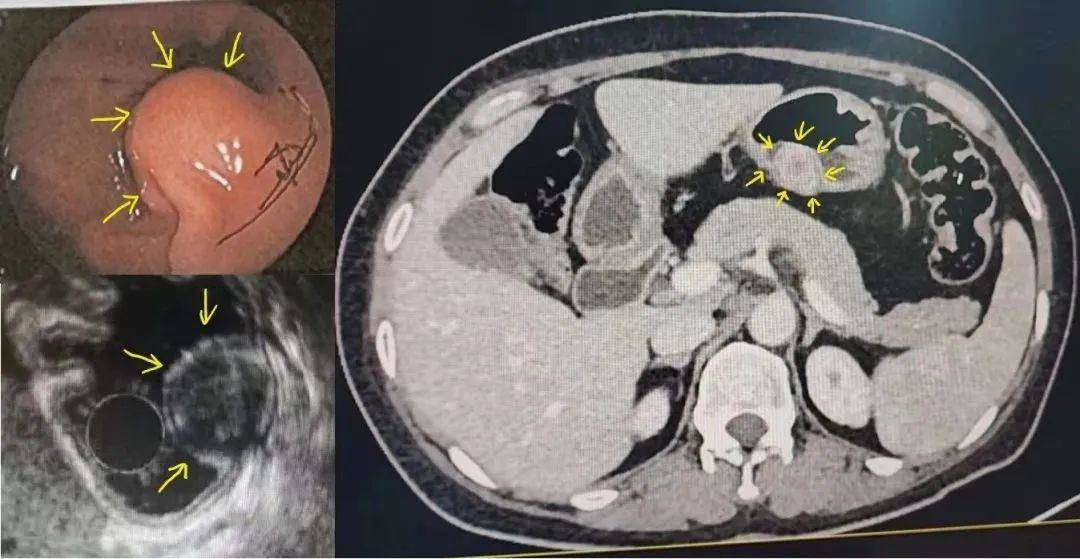

患者周某,女,49岁,1月前外院胃镜体检发现胃体长了一个约2.0×1.5cm的肿瘤,这可把她吓得不轻,急忙赶到深圳禾正医院就诊。消化内科程飞医生在看了周女士的胃镜报告后,考虑具有内镜下切除指征,建议住院进一步评估诊治。完善超声胃镜及上腹低张CT,考虑病变起源于固有肌层,胃腔内外生长,综合判断考虑很大可能是间质瘤。

图1 胃体肿瘤胃镜/超声胃镜/低张CT图片